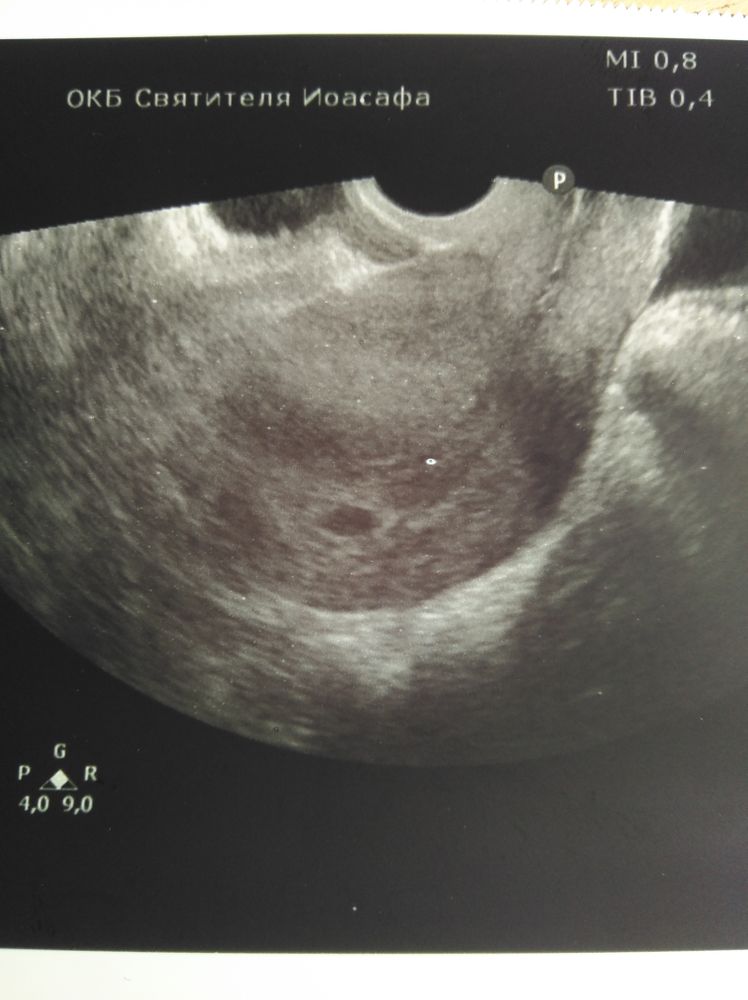

21 дпп побывала баба на узи. Моя ре свалила в отпуск, я конечно в печали, что рыба моя меня покинула, делала узи мне не особо опытная ре. За 2 секунды узи выяснилось, что есть ПЯ 10 мм одно, может 2, но это не точно, но точно есть 1😂😂😂 ЖМ не разглядывали, и вообще все рано, приходите через 2 недели, разберемся... Ну и погадаем на узи, кто сколько видит (узи отвратного качества)

Kate Agaeva, вот теперь понять бы что это за черная хера блуда в матке, рядом с эмбрионом

Kate Agaeva, так сколько ты видишь штук? я вроде 1, а если присмотреться 2...но он какой-то большой, чтож лошадь в 10 мм ре не разглядела?

Шепокляк_, я вижу реально одно то что можно принять за ПЯ

для дилетантов типа меня еще бы матку обвести.

Вижу два 🤷🏻♀️ растите здоровенькими самое главное

Если прям по стрелкам смотреть, то вроде два. Ждём второе УЗИ разгадку🤞

Я вижу два и вижу даже желточные мешочки😁